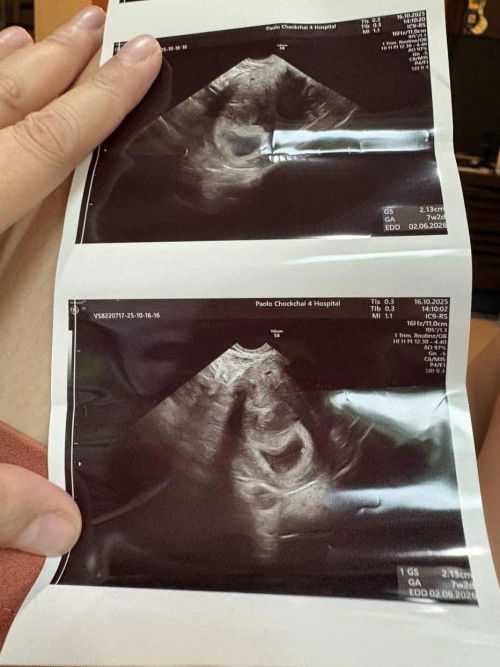

วันนี้ฝากครรภ์ที่โรงพยาบาล อัลตร้าซาวน์ทางหน้าท้อง ช่องคลอด เจอแต่ถุงตั้งครรภ์ แม่ๆมีประสบการณ์นี้มั้ยคะ ว่ามาเจอตัวน้องตอนไหน

ไปฝากท้องเจอแต่ถุงตั้งครรภ์